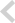

Before

After